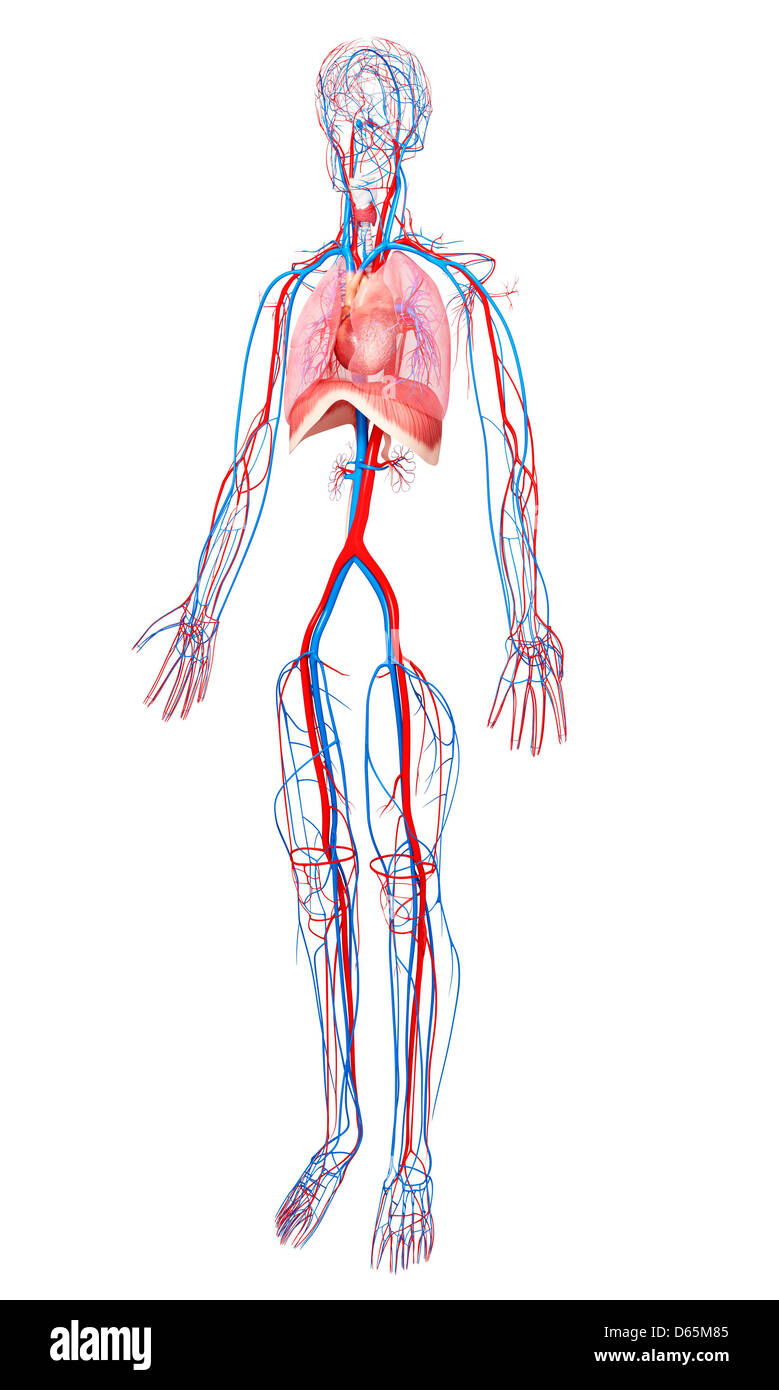

Système cardiovasculaire, artwork Banque D'Imageshttps://www.alamyimages.fr/image-license-details/?v=1https://www.alamyimages.fr/photo-image-systeme-cardiovasculaire-artwork-55415491.html

Système cardiovasculaire, artwork Banque D'Imageshttps://www.alamyimages.fr/image-license-details/?v=1https://www.alamyimages.fr/photo-image-systeme-cardiovasculaire-artwork-55415491.htmlRFD64B0K–Système cardiovasculaire, artwork

Human Anatomy, artwork Banque D'Imageshttps://www.alamyimages.fr/image-license-details/?v=1https://www.alamyimages.fr/photo-image-human-anatomy-artwork-55444709.html

Human Anatomy, artwork Banque D'Imageshttps://www.alamyimages.fr/image-license-details/?v=1https://www.alamyimages.fr/photo-image-human-anatomy-artwork-55444709.htmlRFD65M85–Human Anatomy, artwork